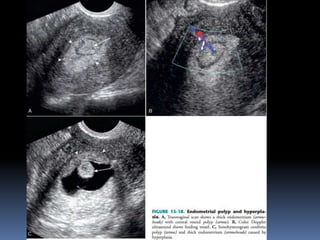

This document contains an image gallery from Dr. Mohit Goel showing various uterine anomalies and ovarian cysts. It includes images of an arcuate and unicornuate uterus, endometritis, a twisted ovarian pedicle, dermoid cysts of varying sizes and echogenicity containing hair, fat, and calcifications, and a combination dermoid cyst showing both mesh and plug structures. The gallery provides ultrasound images of different gynecological conditions for medical education and reference.